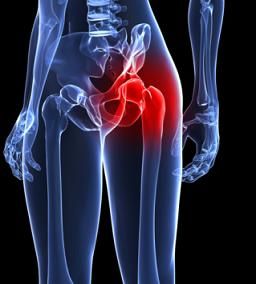

Joint Replacement

Rothman Orthopaedics' Joint Replacement Program is one of the nation's top joint replacement centers, performing more than 17,000 joint surgeries annually.

Because like all surgeries, joint replacement procedures do require some recovery time, they are normally only considered after all other non-surgical options have been discussed and/or attempted. Normally, joint surgery provides significant and wonderful results for the majority of patients. At Rothman Orthopaedic Institute, patients have the advantage of being seen by physicians who have actually helped develop and launch joint replacement techniques and who are considered to be well-renowned authorities on the topic of joint replacement

If you experience pain in any of your joints due to physical activities such as walking, running, and climbing stairs, it may be time to have a Rothman Orthopaedic Institute specialists diagnose your case. Joint replacement may be the answer for you. When simply sitting in a favorite chair or sleeping in your bed causes enough pain to wake you or make your life extremely uncomfortable, joint replacement may be able to get you back to an active lifestyle with less pain.